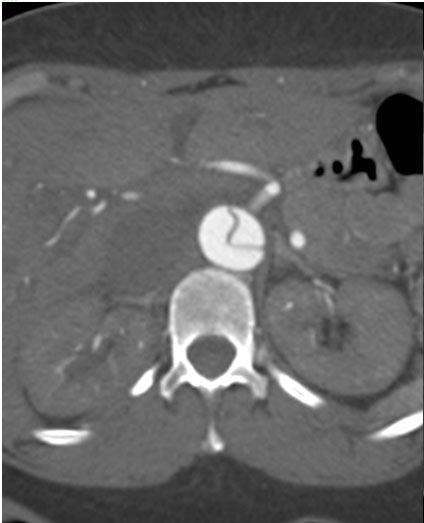

A 49-year-old woman with a history of hypertension and smoking presented to an outside hospital with sudden onset chest pain and hypotension. Computed Tomography/ Angiography (CTA) of the chest and abdomen revealed a type A aortic dissection extending from the ascending aorta to the left common iliac artery. (Figure 1) Of note, there was a significant pericardial effusion and left pleural effusion. Due to her hypotension and tamponade physiology, the patient was rapidly intubated followed by unsuccessful pericardiocentesis. The patient was then transferred to our institution for emergent dissection repair.

Figure 1a-e. Computed Tomography/Angiography (CTA) at

presentation demonstrating a type A aortic dissection.

Figures 1b-d. Axial CT cuts demonstrating the dissection continuing into the left common iliac artery.